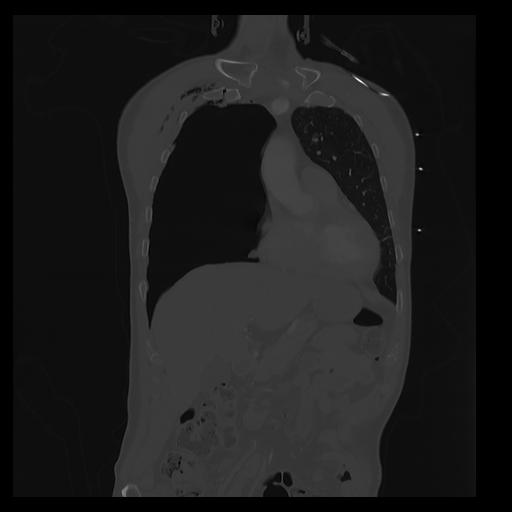

32 PULMON,CE,Coronal,3.000,PULMON,Coronal,